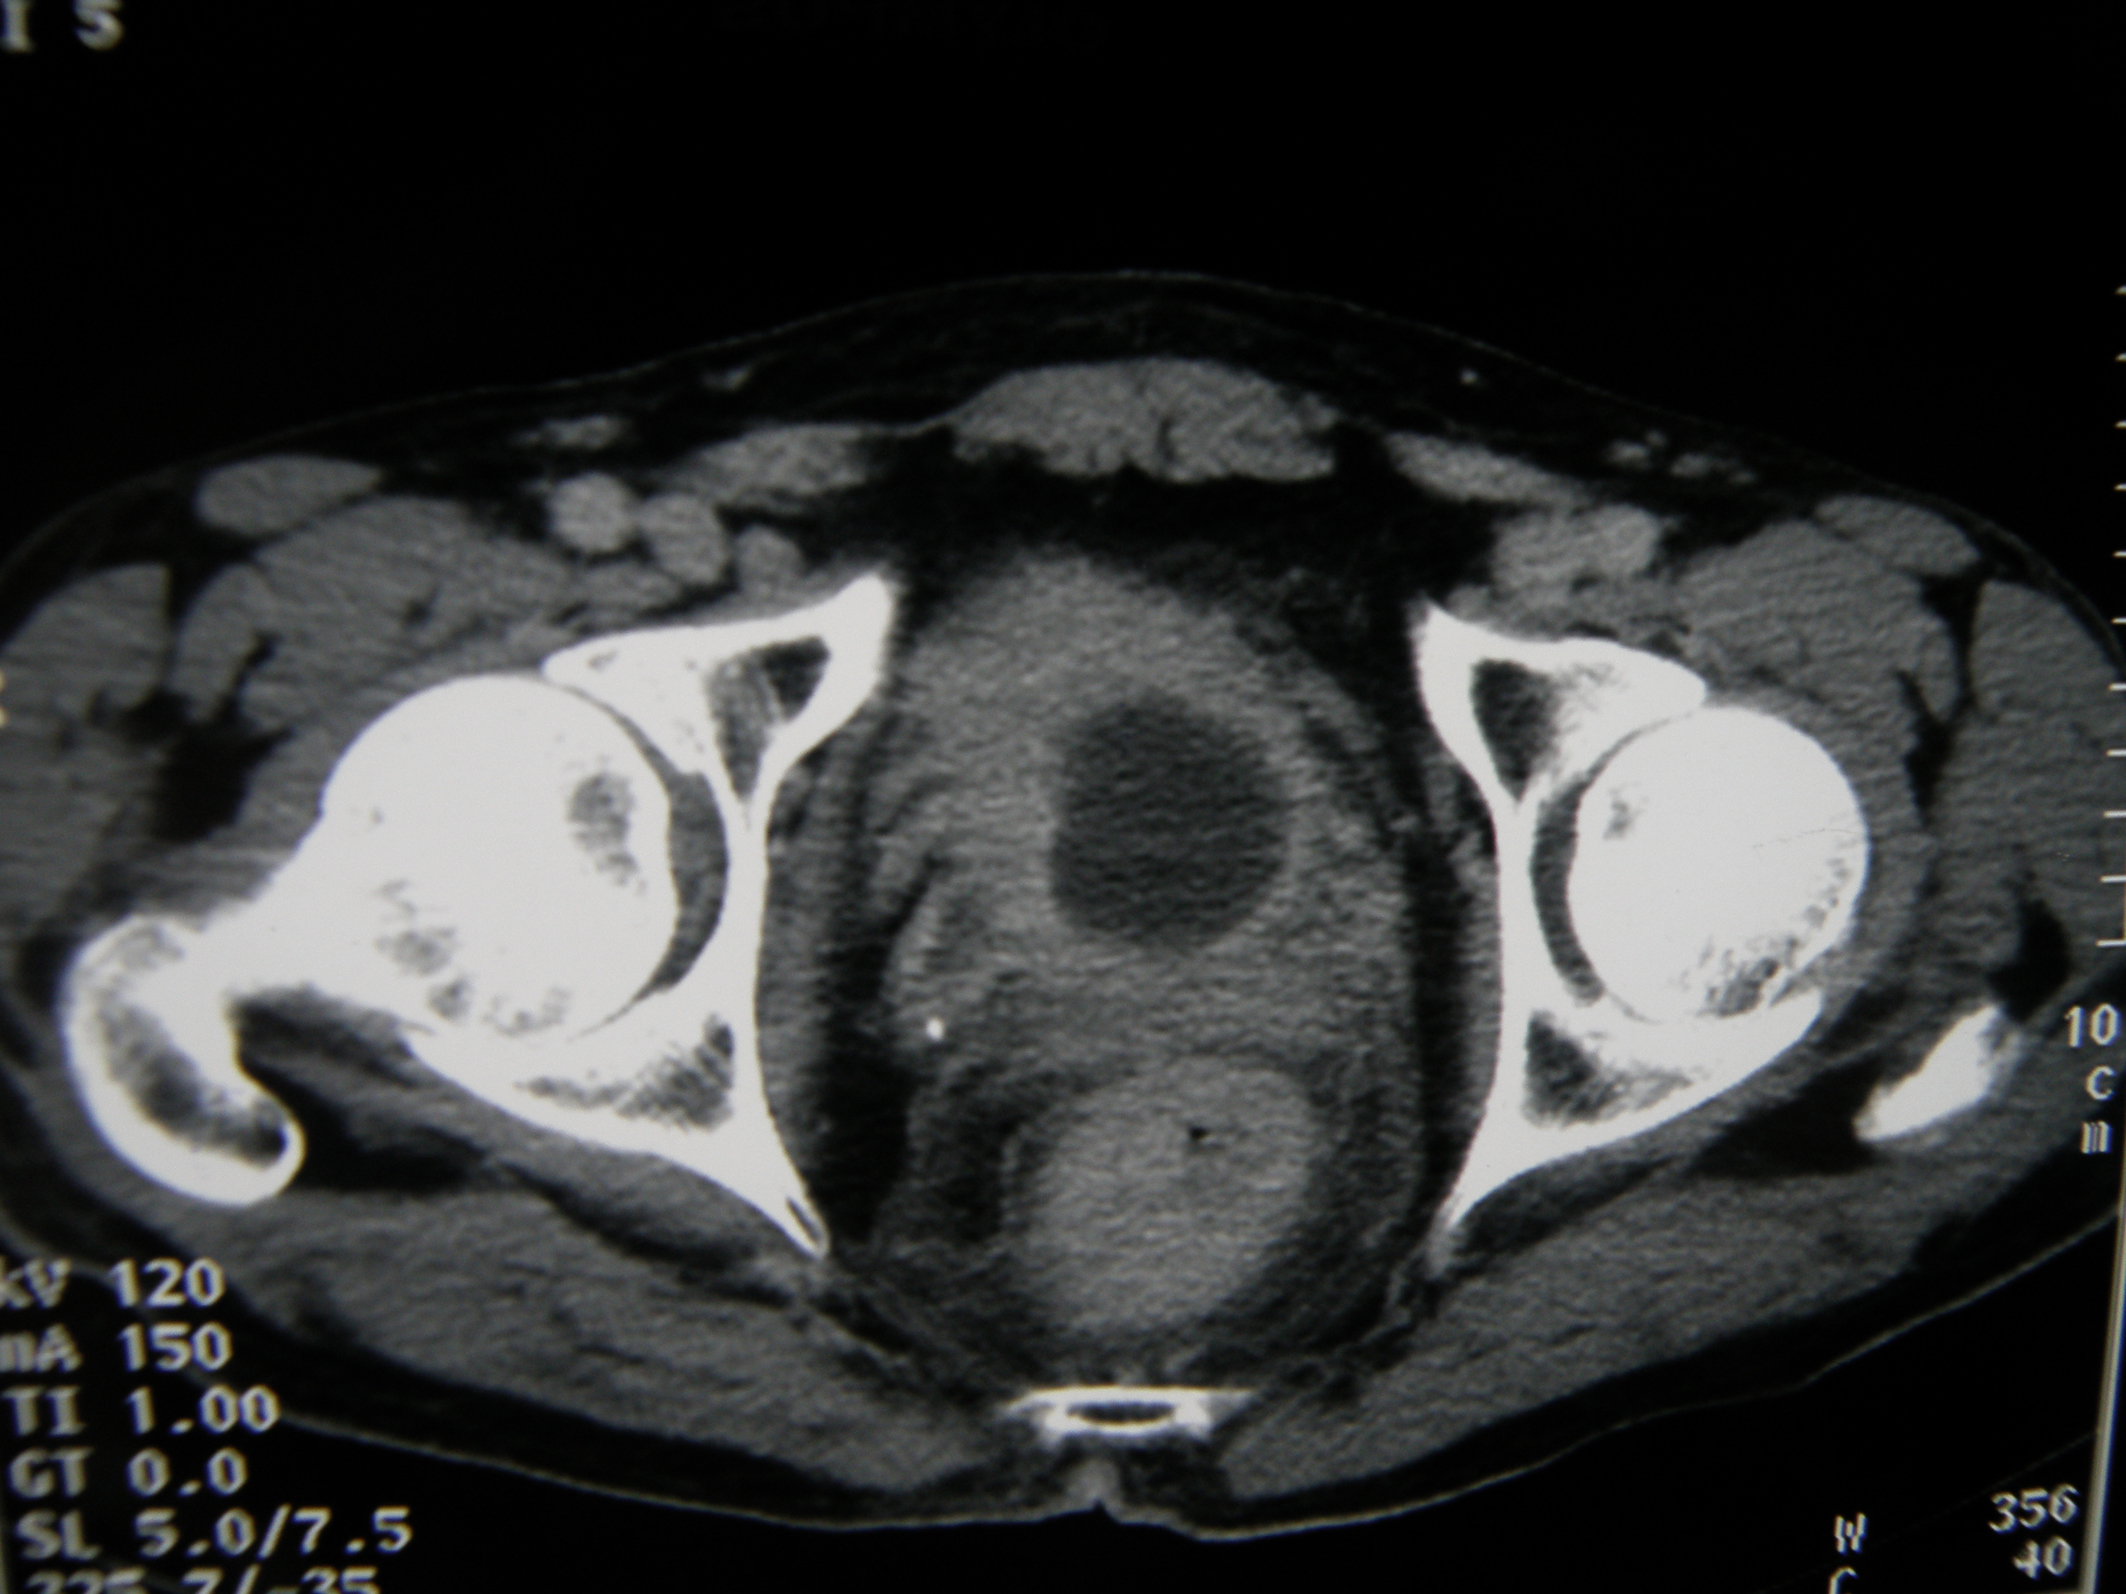

A 67-year-old man presented with gross hematuria and irritative urinary symptoms. He had a 35-pack year history of smoking and no family history of genitourinary malignancy. Cystoscopy revealed an extensive polypoid mass of the bladder. Computed tomography scan showed an extensive thickening of the bladder wall with extension to the perivesical fat (Fig. 1). Pathologic examination of the surgical specimens of transurethral resection was consistent with the diagnosis of poorly differentiated carcinoma infiltrating the muscle and radical cystoprostatectomy with bilateral lymph node dissection was performed. Grossly, there was a 4 x 4 x 2 cm polypoid solid mass in the dome with an important thickening of the bladder wall. Microscopically, the tumor was composed of sheets of uniformly small, round, mitotically active cells with overlapping nuclei lacking prominent nucleoli (Fig. 2). Areas of necrosis were found. Immunohistochemical stains showed immunoreactivity of most of tumor cells for synaptophysin (Fig. 3) and neuron specific enolase. On the basis of these morphological and immunohistochemical findings, he was diagnosed of primary pure SCC of the bladder. The tumor invaded the muscle and the perivesical fat. Computed tomography of the lung and bone were normal. There were no lymph nodes metastases. The patient received thirty cycles of pelvic hemostatic radiotherapy and eight cycles of platinium-based chemotherapy. Three months later, he developed bone, renal and adrenal metastases.

![]() Click for large image | Figure 1. Computed tomography scan showing an important thickening of the bladder wall. |